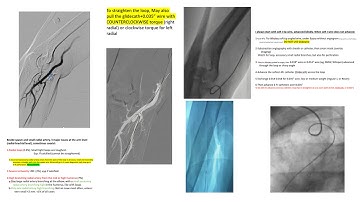

Managing the alpha radial artery loop with BAT( balloon assisted technique)